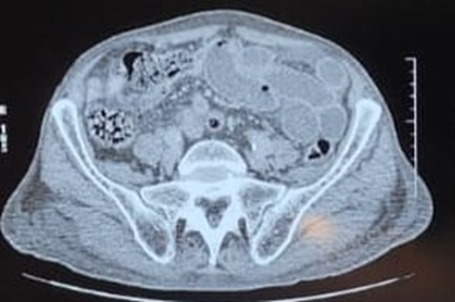

A contrast-enhanced CT scan demonstrated circumferential and irregular bladder wall thickening (maximum thickness 24 mm) involving a diverticular bladder dome measuring 34 × 25 mm. The diverticulum exerted a mass effect on an adjacent ileal loop, resulting in subtotal luminal occlusion and upstream small bowel distension with air-fluid levels (31 mm maximum diameter). A “pearl sign” was visible at the site of obstruction.

Another diverticulum in the right posterolateral bladder wall, measuring 30 mm in diameter, contained microcalcifications and was encasing the ureteral orifice and pelvic ureter, which showed no upstream dilatation due to the nephrostomy. The thickened bladder wall appeared to infiltrate the prostate and was in intimate contact with the anterior rectal wall, which exhibited submucosal edema.

The findings were consistent with small bowel mechanical obstruction secondary to mass effect from a diverticulum infiltrated by urothelial carcinoma.

Figure 1. Axial pelvic CT scan showing circumferential thickening of the bladder wall with suspected infiltration and a diverticulum of the bladder dome.